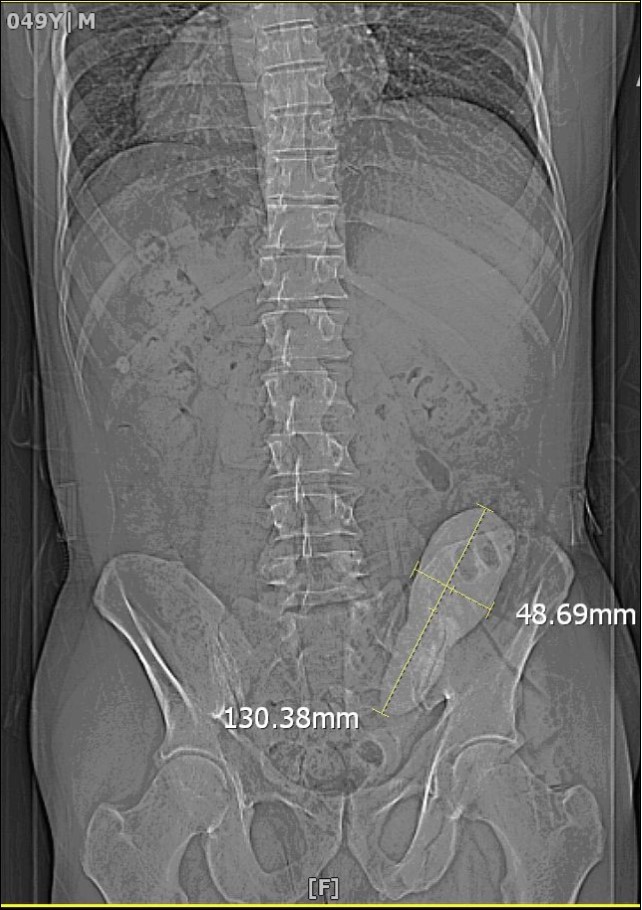

We report a case of a gentleman with spina bifida who underwent urinary diversion in the form of an ileal conduit as a child and presented 40 years later with worsening renal function that was picked up by his general practioner during routing investigations. Clinical examination revealed a hard mass superomedial to the right parararectal stoma. An initial ultrasound scan showed bilateral hydronephrosis and a possible calculus in the conduit. A subsequent CT KUB showed a 13 cm x 4 cm calculus occupying most of the conduit causing outflow obstruction (Figure 1). He also had a 2cm left renal calculus. Following a Foley catheter insertion into the stoma under image guidance, his renal function returned to normality. The patient was counselled for both the open and endoscopic approach.